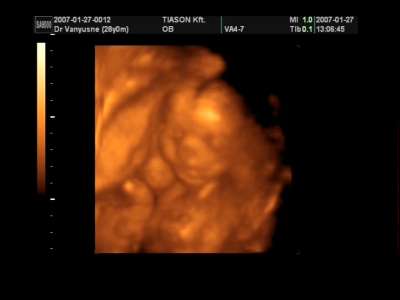

Babancs: Nagyon ééééééééédes, milyen szépen látszik a kis pofija